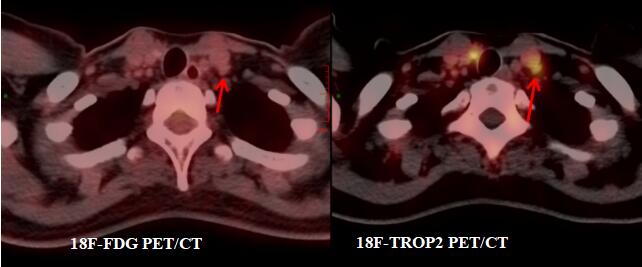

(江叶青报道)近日,江西省肿瘤医院核医学科收治一名甲状腺癌二次手术患者宋某。2022年,宋某因颈部包块在当地医院行左侧甲状腺癌根治术,术后病理确诊为甲状腺微小乳头状癌。出院后定期随访复查,但今年9月复查显示颈部淋巴结转移可能,10月,患者转入江西省肿瘤医院头颈肿瘤外科二病区接受右侧甲状腺手术及颈部淋巴结清扫,术后病理提示右侧甲状腺亦为微小乳头状癌,且颈部淋巴结存在转移性病变。为评估病情并指导后续碘-131治疗,同期为患者行18F-FDG与18F-TROP2 PET/CT显像,结果呈现鲜明对比:

左侧颈部III区淋巴结:FDG代谢未见增高,但TROP2代谢明显增高,穿刺洗脱液Tg检测强阳性(7658 ng/ml)。明确为隐匿的甲状腺癌转移灶。

本例突出展现了18F-TROP2 PET/CT在甲状腺癌术后评估中的独特优势:

高特异性与互补性:TROP2是一种在多种实体瘤中呈高表达的跨膜糖蛋白,其异常表达与肿瘤增殖、侵袭及患者不良预后密切相关,在正常组织中几乎不表达。18F-TROP2 PET/CT可特异性识别表达此靶点的癌细胞,尤其能发现那些FDG代谢不活跃的隐匿转移灶(如本例III区淋巴结),弥补了传统18-FDG PET/CT的不足。

优化临床决策:它能更准确地区分转移性淋巴结与非肿瘤性病变,避免误判。这为精确制定后续治疗策略提供了关键依据,是迈向甲状腺癌精准诊疗的重要工具。